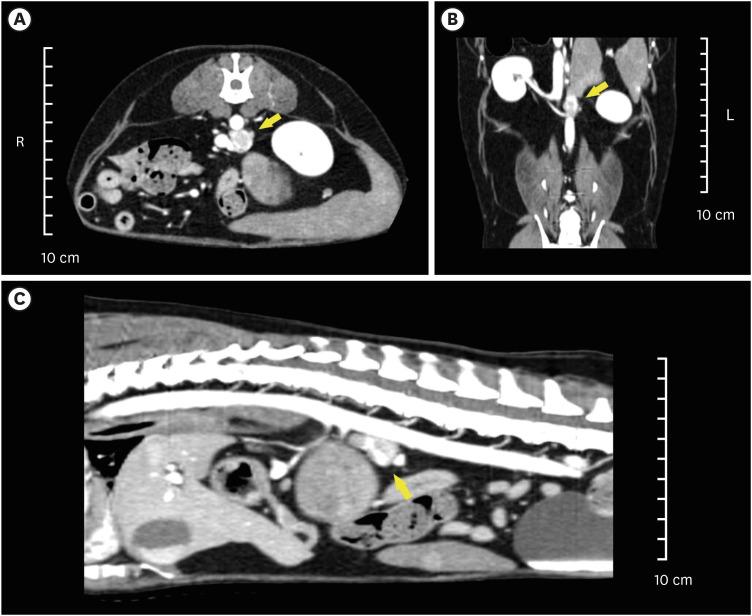

A 10-year-old, 6.87 kg, spayed female poodle was referred for an abdominal mass and eight episodes of vomiting. Computed tomography revealed masses in the spleen and left adrenal gland. Based on the plasma normetanephrine levels, the patient was diagnosed with pheochromocytoma. Subsequently, a total splenectomy and left adrenalectomy were performed. A dose of 5 mg/kg ICG was administered intravenously 24 h prior to surgery. Using ICG allowed visualization of tumor margins, aiding in complete resection and minimizing anesthesia-related risks.

一只 10 岁、6.87 公斤的已绝育雌性贵宾犬因腹部肿块和 8 次呕吐而被转诊。计算机断层扫描显示脾脏和左肾上腺有肿块。根据血浆去甲变肾上腺素水平,该犬被诊断为嗜铬细胞瘤。随后进行了全脾切除术和左肾上腺切除术。手术前 24 小时静脉注射 5mg/kg 的 ICG。使用 ICG 可以观察到肿瘤边缘,有助于完全切除肿瘤,并最大限度地降低麻醉相关风险。